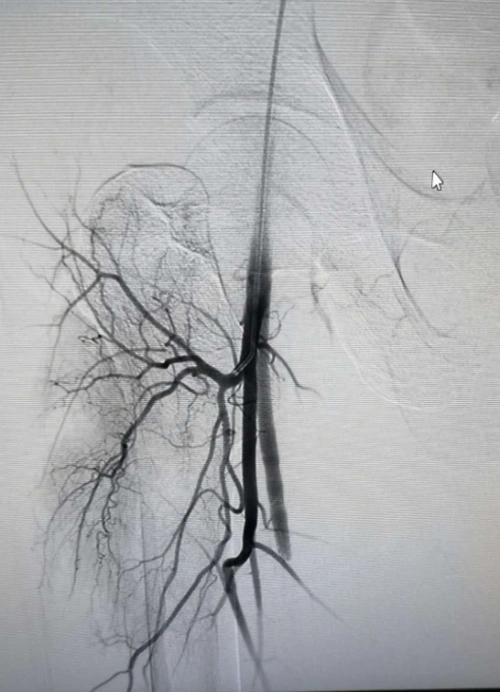

我院完成首例股骨头坏死动脉造影